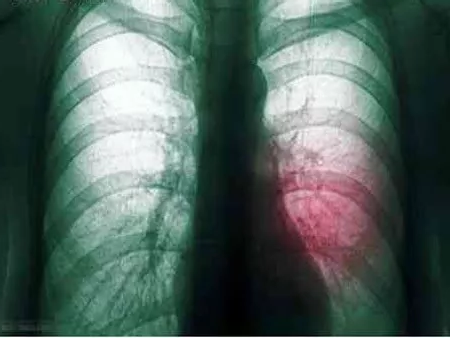

我院呼吸科主治醫(yī)生孟醒在分析2位患者的胸部CT結(jié)果并結(jié)合了解他們的生活史后,診斷他們得了肺膿腫。

在得知診斷結(jié)果后,兩位患者以為自己得了肺癌,不知所措,甚至感覺人生走到頭了。在此,孟醒提醒:肺膿腫和肺腫瘤完全是兩個不同的概念,大部分通過抗生素治療即可痊愈。

“肺膿腫是一種良性的肺部感染性疾病,由于病原菌多為厭氧菌,所以痰液常常帶有腥臭味?!?/span>孟醒介紹,在新中國剛成立前后,肺膿腫還是比較常見的,隨著人們生活水平的不斷提高,衛(wèi)生條件的不斷改善,現(xiàn)在得肺膿腫的病人已經(jīng)很少了。

他進一步解釋,既然肺膿腫是一種感染性的病變,只要根據(jù)痰液細菌培養(yǎng)的結(jié)果,選擇敏感的抗生素,肺膿腫就是可以治愈的。肺膿腫如長期(大于3個月)內(nèi)科保守治療效果不佳,或存在惡性腫瘤、大咯血、膿胸,則需要外科手術(shù)治療。“在我工作十余年來,從來沒有一例肺膿腫患者需要外科手術(shù)治療的?!泵闲烟嵝褟V大市民,吸煙有害健康,預(yù)防肺膿腫最好要戒煙,增強機體免疫力,同時要注意口腔衛(wèi)生,防止誤吸口、鼻、牙齦炎癥形成的膿性分泌物和嘔吐的胃內(nèi)容物等,此外,肺炎早期要積極給予抗生素治療。